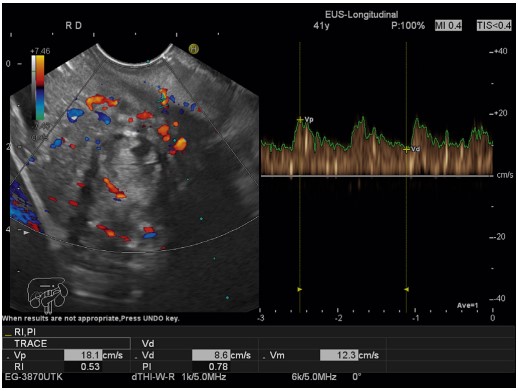

Contrast-Enhanced Harmonic EUS

Contrast-enhanced harmonic EUS utilizes specialized software with low mechanical index capabilities, established for differentiating focal pancreatic masses. This method enhances the visualization of vascular structures and blood flow, leading to more accurate diagnoses.